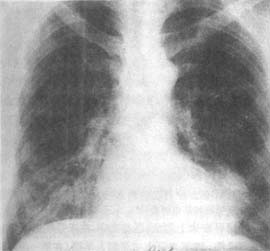

2.內鏡檢查可以發現膈上食管憩室有無炎症、潰瘍形成、憩室癌和食管梗阻的程度;病人有上消化道出血,內鏡檢查可以明確出血的來源。體積大的膈上食管憩室可使食管發生移位,因此內鏡檢查有發生憩室穿孔的可能,檢查過程中須特別小心。膈上食管憩室可並發潰瘍、出血或自發性憩室穿孔。有的病例發生憩室出血後出血較為嚴重,須手術切除憩室後方能控制出血。憩室本身可發生返流和誤吸,而誤吸可引起吸入性肺炎和肺膿腫。據文獻報導,膈上食管憩室可發生腫瘤,如發生纖維瘤、平滑肌瘤和鱗癌。體積較大的憩室內食物和分泌物鬱積或滯留、慢性感染以及憩室內容物腐敗等因素可能促進憩室發生癌腫。食管鋇餐造影顯示膈上食管憩室的輪廓不規則或其形態較前縮小,疑有憩室癌腫發生時,應及時行食管鏡檢查。